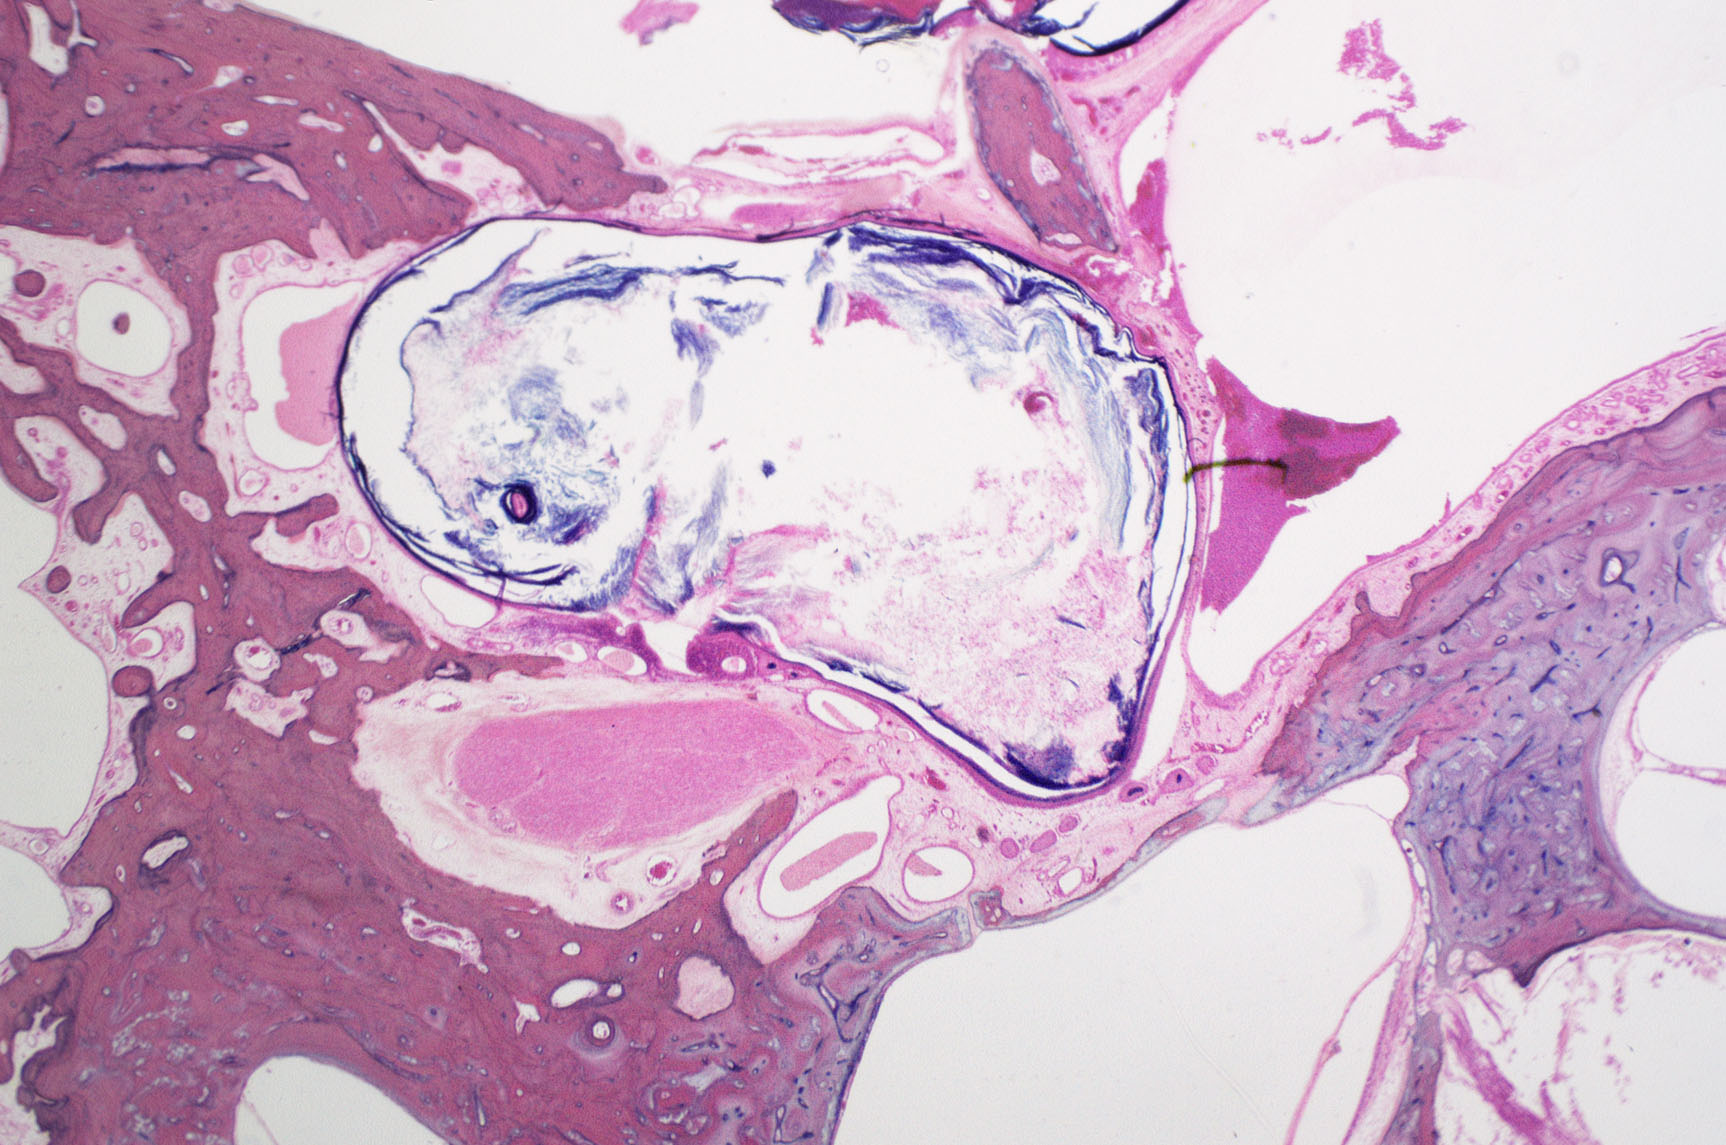

Paparella Otopathology & Ear Pathogenesis Laboratory: Otitis Media

Founded in 1963 by Dr. Michael Paparella, the University of Minnesota’s Paparella Otopathology & Ear Pathogenesis Laboratory has made groundbreaking contributions to the field of otology and neurotology, pioneering research that advances our knowledge of hearing and balance disorders. Notably, the Lab spearheaded research that demonstrated the hearing and vestibular sequelae secondary to otitis media, and introduced the theory of the otitis media continuum, which has reshaped our understanding of pathophysiological mechanisms of otitis media. The lab also introduced the concept of silent otitis media, highlighting how the condition can progress without noticeable symptoms.